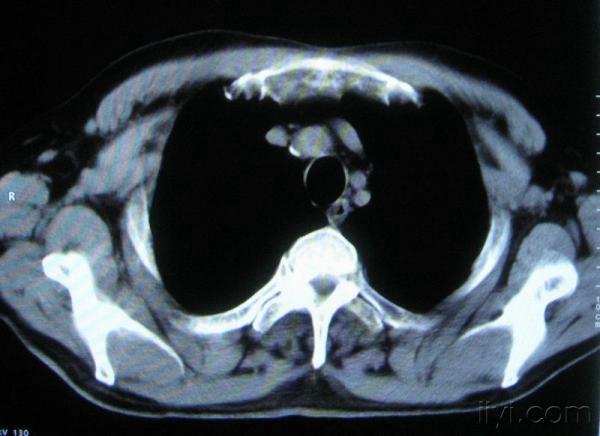

男。60岁,胸片示支气管炎治疗后复查CT。

应该是淋巴结没问题的,中心液化坏死是有这种情况的~~胸科常见到

你指那个肯定是淋巴结,中央系坏死,这很常见,特别在双侧腹股沟会经常看到。这个双侧腋窝及纵隔见多发小淋巴结征。

根据位置考虑应该是淋巴结,密度不均,是因为肿大的淋巴结中心液化坏死